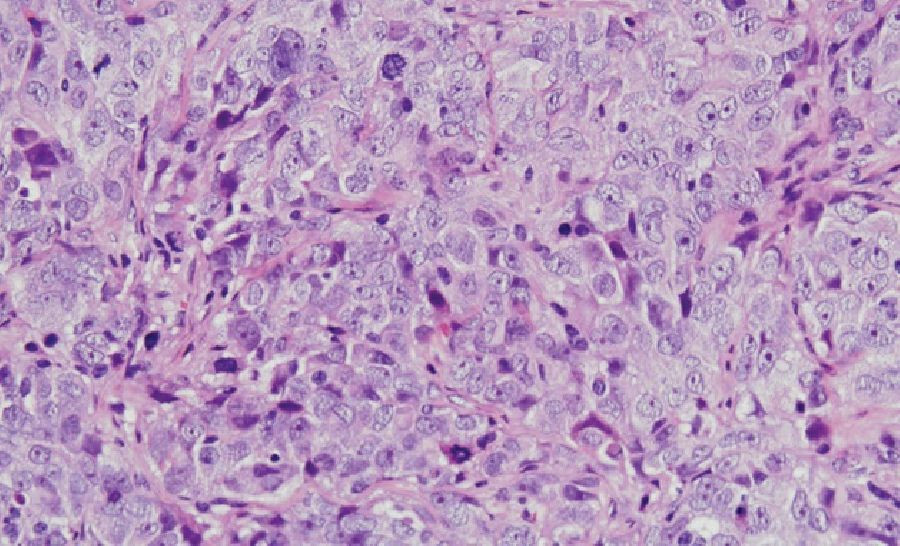

El cáncer de ovario es uno de los cánceres ginecológicos más mortales en las mujeres. Cada año se diagnostican en todo el mundo unos 300.000 nuevos casos y se producen unas 200.000 muertes. La mayoría de los cánceres de ovario son de origen epitelial y, de ellos, más del 70 por ciento se catalogan como tumores de ovario de alto grado y suelen diagnosticarse en un estadio avanzado, dado que no presentan síntomas ni signos específicos en su fase inicial. Estas circunstancias le confieren un mal pronóstico y exigen el desarrollo de nuevas estrategias terapéuticas para combatir la evolución de la enfermedad.

Esto llevó a la identificación de una proteína, denominada WNK1, que se encontraba anormalmente activa en las líneas celulares analizadas. Este resultado impulsó el análisis del estado de activación de esta proteína en tumores de pacientes diagnosticadas con diferentes tipos de cáncer de ovario en el Hospital Universitario de Salamanca, revelando que la activación anormal de WNK1 afectaba drásticamente a la supervivencia de las pacientes.